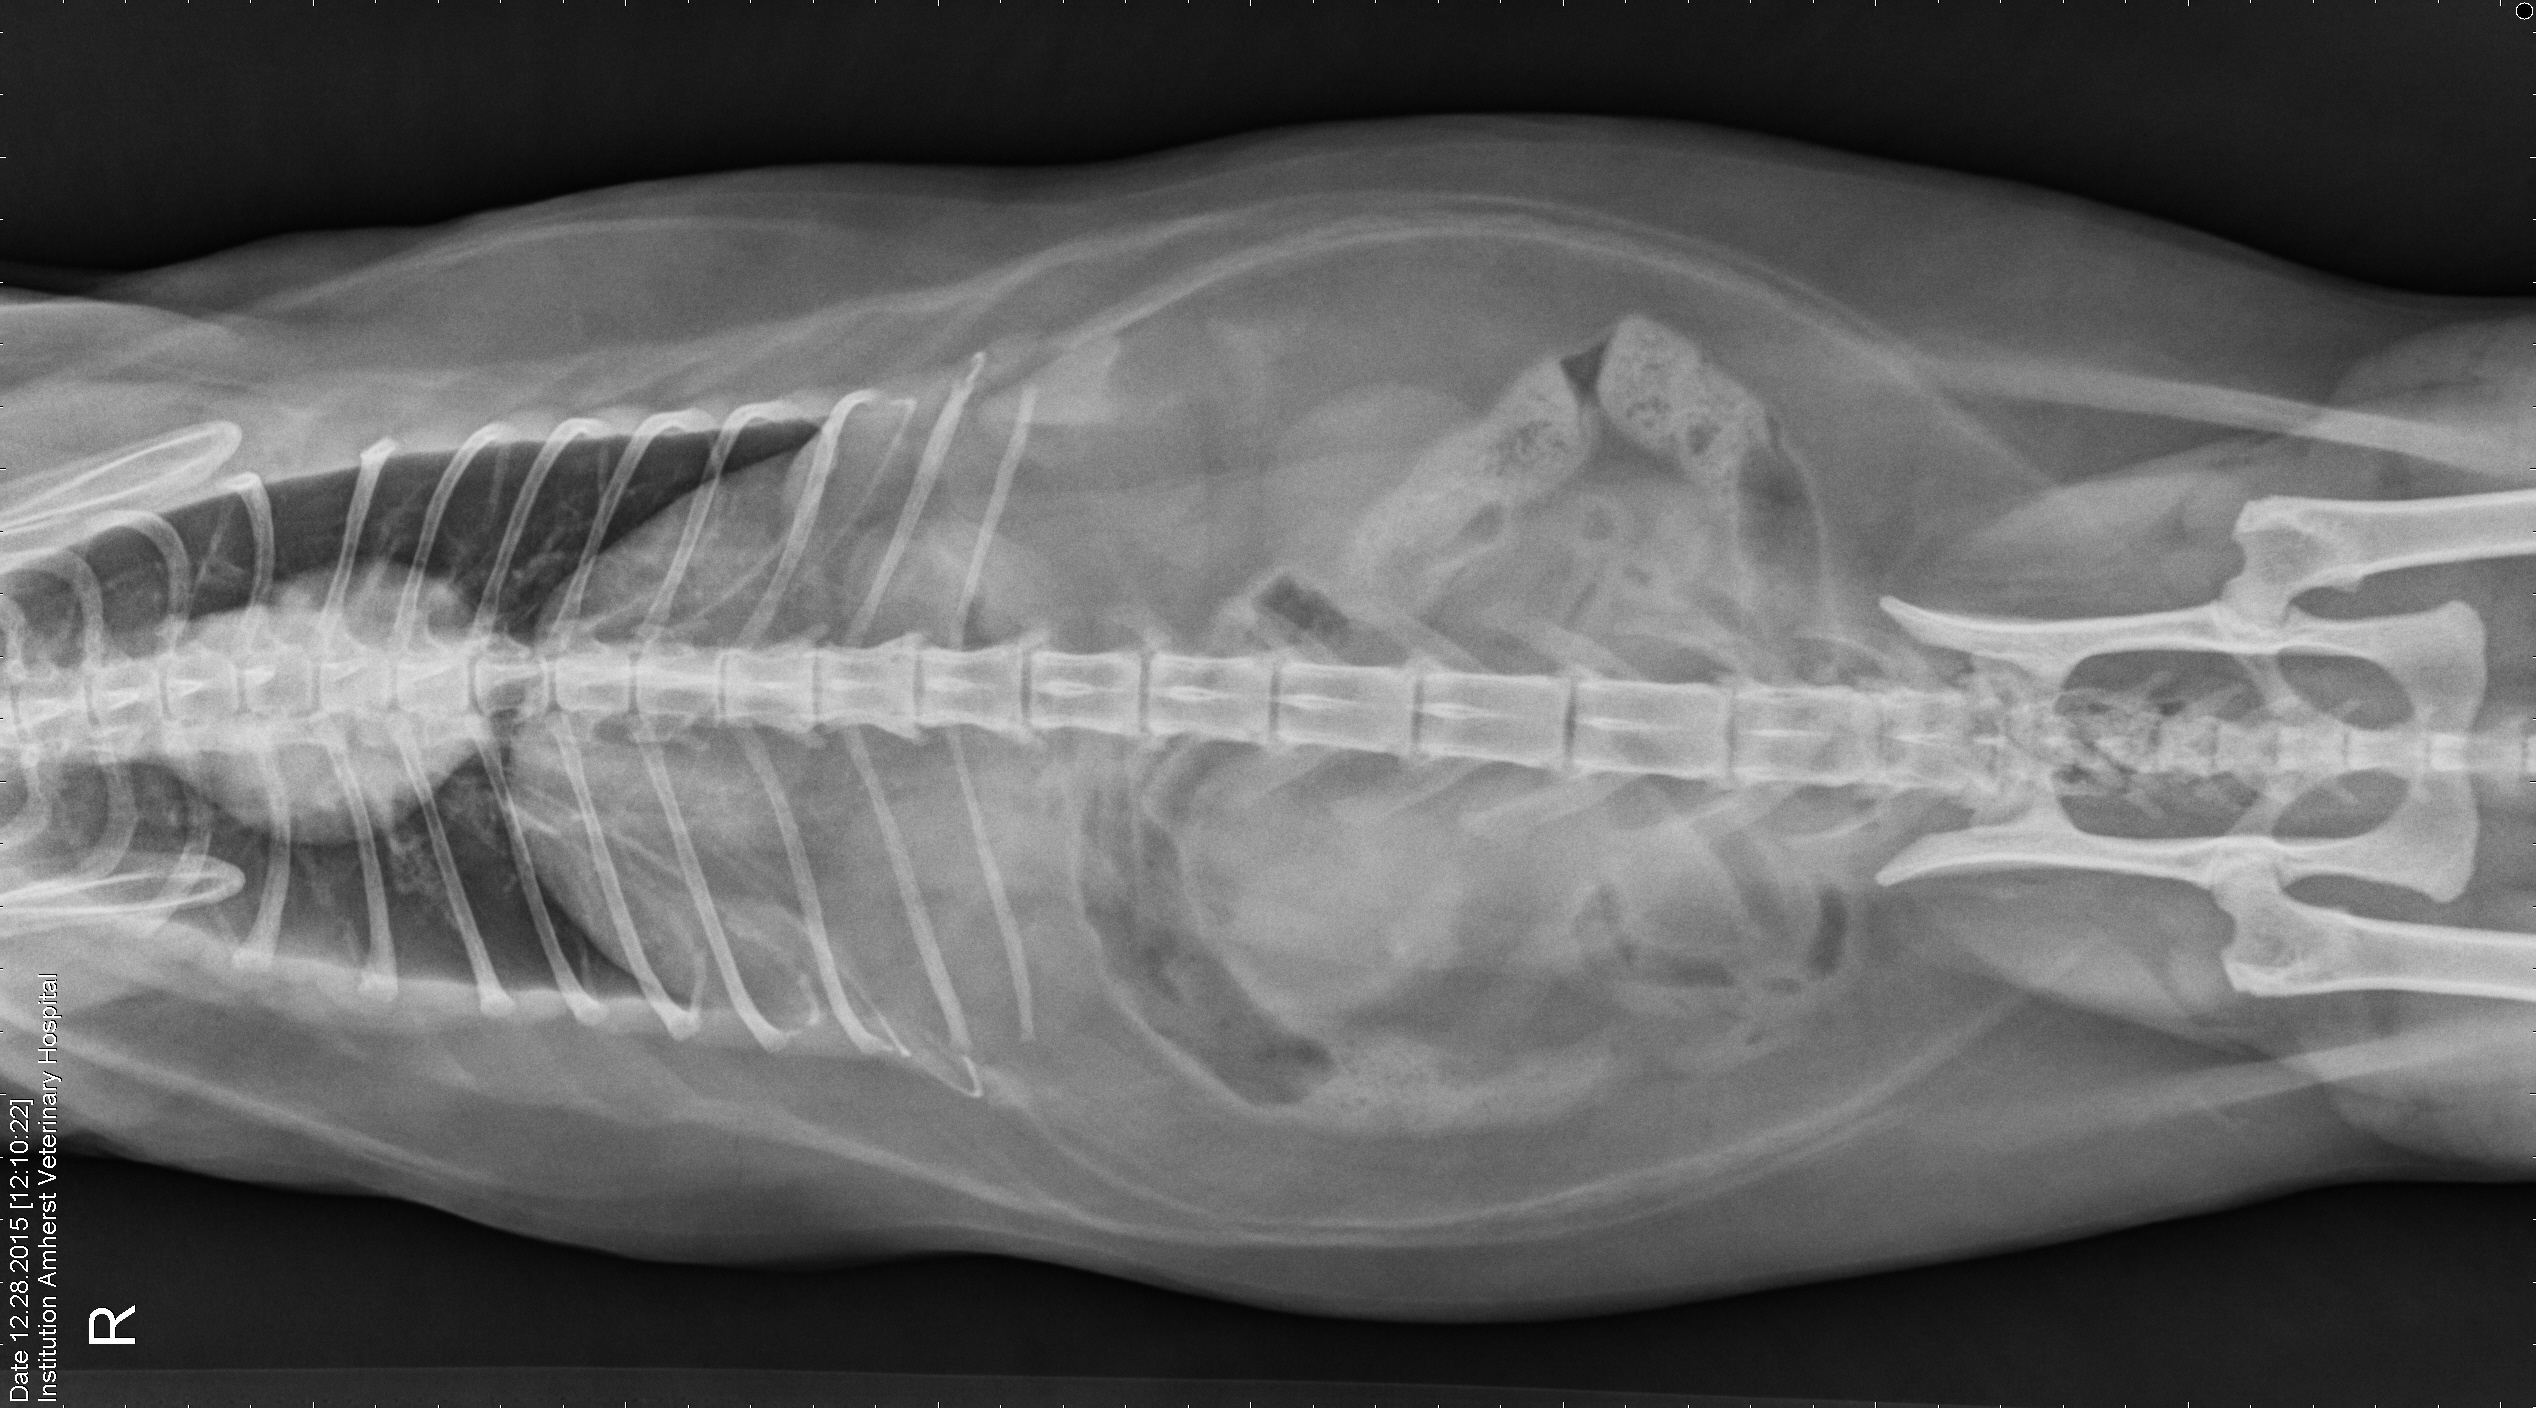

Here she is. In all her radiograph splendour.  Fuius Schmeezer Exarchas.  Cat Pictures    “Radiograph”. I wondered about that. Still just an “X-Ray”. Nothin to see here.

Radiograph Amherst Veteranary

Fuius Radiograph Amherst Veterinary